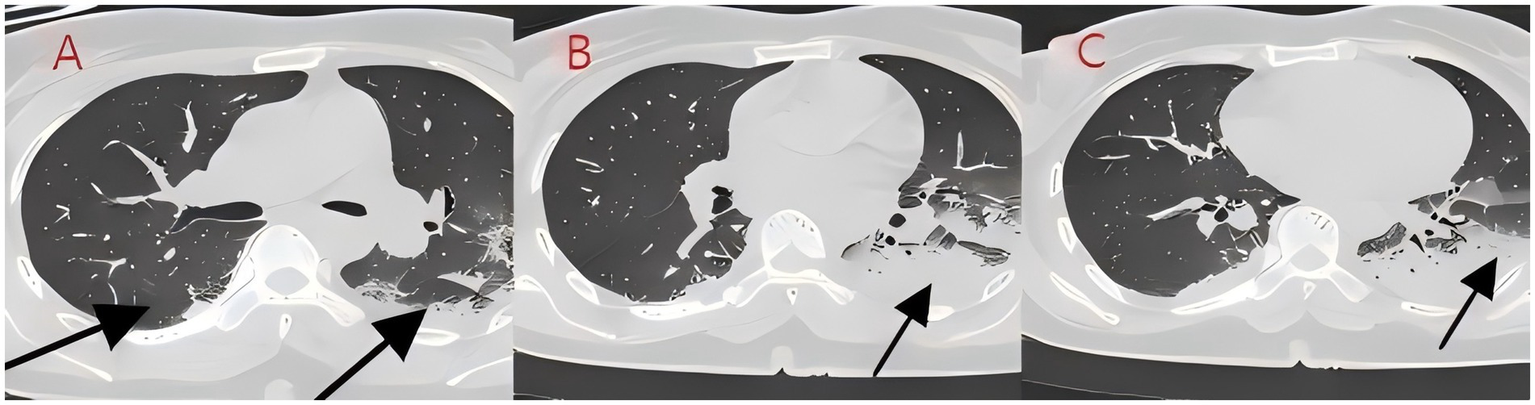

We present another case of a middle-aged Asian woman who was admitted to the hospital after drowning and inhaling a large amount of sewage. The patient inhaled stagnant wastewater from domestic sewage discharge. She showed noticeable chills and vomited a black, muddy substance while being transported. Upon admission, head, chest, and belly CT scans, along with related blood testing, were performed. Due to her critical condition, she was transferred to the ICU. Physical examination at admission revealed that her body temperature was 36.3 °C, pulse was 81 beats/min, respiration rate was 16 breaths/min, and blood pressure was 112/61 mmHg. The patient was conscious but had signs of fatigue and significant chills. Her scalp skin had a 3 × 1 cm tear. Her cardiac examination was normal; however, lung auscultation revealed bilateral wet rales, which were more pronounced in the left lung area. Furthermore, she had normal limb muscle strength and tone. There are no signs of meningeal irritation. The patient denied a history of underlying medical conditions or food or drug allergies. Emergency CT scan showed subarachnoid hemorrhage, and infectious lesions were observed in both lungs, with the left lung being primarily affected (Figure 2). The left lung also exhibits patchy, hyperdense shadows and a little pleural effusion. Moreover, her potassium levels were 2.96 mmol/L, and osmotic pressure was 288 mOsm/Kg. Similarly, the coagulation characteristics analysis revealed a D-dimer level of 3,990 μg/L. Arterial blood gas analysis showed her lactate level to be 2.50 mmol/L, pH (T) to be 7.37, pCO2 (T) to be 40.60 mmHg, and pO2 (T) to be 55.60 mmHg. Her complete blood count and C-reactive protein test results revealed that her white blood cell count was 19.77 × 109/L, whereas the C-reactive protein level was 0.51 mg/L. At admission, she was diagnosed with traumatic subarachnoid hematoma, aspiration pneumonia, type I respiratory failure, and drowning. After she was admitted to the ICU, she was given anti-infective drugs: cefoperazone–sulbactam (3.0 IV via VP every 8 h) combined with fluconazole (FLZ) injection [0.4 g via IV drip (IV gtt) once daily] to fight infection. After 2 days, the patient was re-examined due to stable vital signs, and chest CT revealed that lung infections had improved compared to the initial findings (Figure 3). After consultation with a clinical pharmacist, cefoperazone–sulbactam was changed to biapenem (0.3 g IV gtt qd every 8 h) combined with FLZ (0.4 g IV gtt qd) to remove the microorganisms. After 5 days, due to recurrent fever, she was transferred to the respiratory department and her anti-infection regimen was adjusted to oral therapy: meropenem (Mpm; 1 g IV every 8 h) combined with voriconazole tablets (400 mg every 12 h). After ruling out contraindications, tracheoscopy was performed on LB2 and LB3, with brushing and BAL of the left upper lobe. Furthermore, cytology, acid-fast stain, cell differential count, culture, and mNGS analysis of the lavage fluid were performed. Both lungs indicated improved infection lesions in the chest re-examination (Figure 4). The patient was discharged after 12 days of admission due to her inability to pay hospitalization expenses. The lavage fluid mNGS revealed the presence of T. whipplei (sequence number: 4683) and Aspergillus flavus (sequence number 9). During hospitalization, the primary medication was a dimorphic dose, but only the last dose was consistent with the mNGS report (Figure 5).

Figure 4. (A–C) Chest CT after 8 days of treatment (case 2). The infection in both lungs has significantly absorbed, large areas of consolidation shadows have been absorbed, and only some cord-like shadows can be seen.